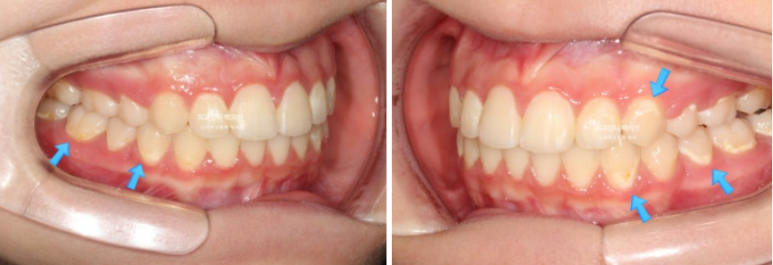

23.09

앞니가 두 개가 아주 커보입니다.

사실 환자분의 앞니가 크진 않습니다. 치아는 입안에서 철저한 원근법을 따르기 때문에 위치적으로 다른 치아에 비하여 앞으로 튀어나와 있으면 상대적으로 커보입니다.

앞니 돌출이 심한편입니다.

돌출이 위에만 국한되어 있어 위에만 작은어금니 2개 발치 후 교정하기로 했습니다.

치료시작 9개월째 모습입니다.

파란 화살표의 브라켓 주변 희끗한 부분은 양치가 잘 안되어 탈회된 부분입니다.

치아가 삭았다라고도 하고 정체는 초기충치입니다.

24.06

발치공간은 절반정도 닫혔습니다.

아래는 비발치로 배열 진행중입니다.

중심선은 잘 맞습니다.

유난히 커보이던 앞니는 돌출이 해소되고 가지런해지면서 누명을 벗었습니다.

25.06

교합은 좋습니다.

간혹 작은어금니 발치교정은 4개를 빼야 교합이 맞지 않나에 대한 질문을 듣는데 위에만 돌출인 경우 위에만 2개 빼는 교정도 좋은교합으로 마무리 되는 교정이랍니다.

그런데 파란화살표에 교정 중 양치가 잘 안되던 부분에 하얀 자국이 보이시죠. 브라켓이 붙어있던 네모모양을 제외한 주변이 초기충치로 얼룩덜룩 해진 모습입니다.

앞으로 관리가 잘 된다면야 큰 문제는 없겟지만 일부는 레진치료가 필요합니다.